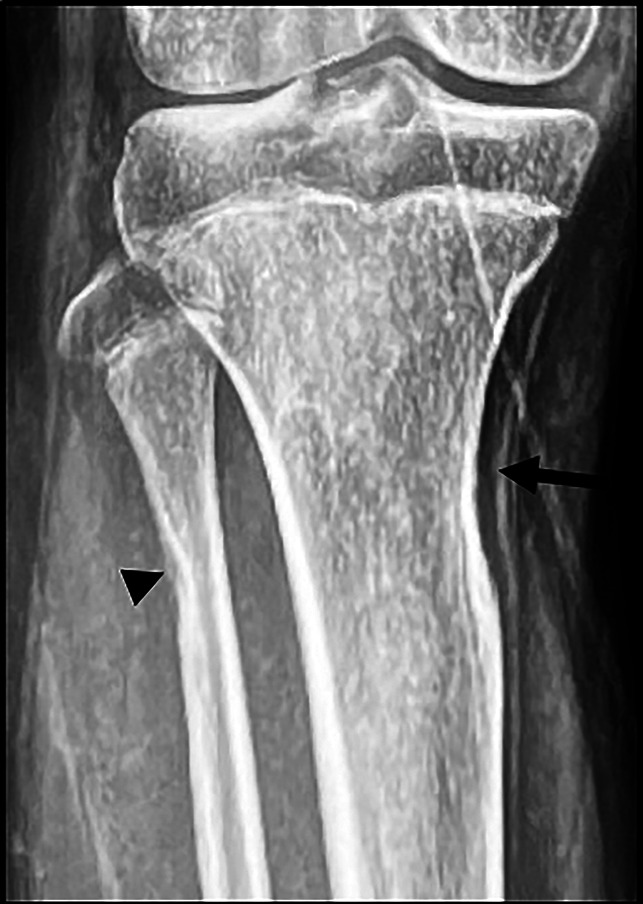

这个报告描述了一个15岁的青春期男孩患有1型神经纤维瘤病,在他的身体的右半部分有区域体细胞嵌合。其独特的临床特征是下肢广泛性半肥厚,伴长骨进行性生长迟缓,导致肢体缩短。患者成功地接受了肢体延长手术。据我们所知,这是第一篇报道1型神经纤维瘤病患者肢体延长手术的文章,该患者因36%的基因缺失而在同一肢体上出现两种主要的相反生长现象。

This presentation describes a 15-year-old adolescent boy with neurofibromatosis type 1 with regional somatic mosaicism in the right half of his body. The unique clinical features are highlighted by generalized hemihypertrophy of the lower extremity in association with progressive growth retardation of long bones, which results in limb shortening. The patient successfully underwent limb lengthening. To our knowledge, this is the first neurofibromatosis type 1 article to report of a limb-lengthening procedure in a patient with two major and opposite growth phenomena on the same limb caused by a 36% gene deletion.